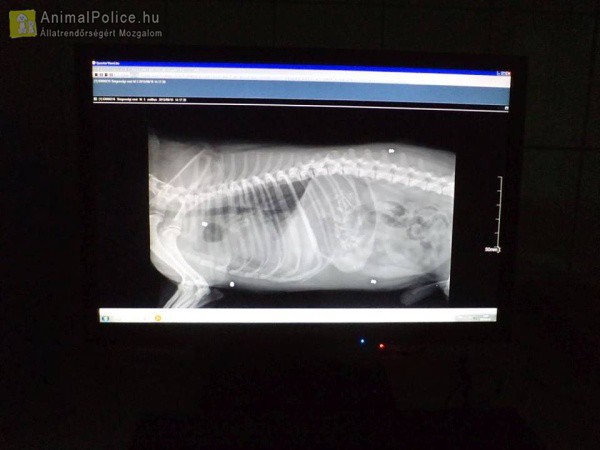

A sebesült, kihűlt kutyába négy golyót mutatott ki a röntgenKedd este a Csabai Állatvédők találták egy sebesült, kihűlt kutyát Békéscsabán. Az állat szörnyű állapotban volt: a testében négy golyót mutatott ki a röntgen, de ennél valószínűleg több is lehet beágyazódva a kutyus testében. Egy lőtt sebe még vérzett a többi már be volt ágyazódva. Megrugdosták vagy elgázolhatták, mert a lövésből származó sérülések mellett tüdő- és agyvérzése is van. A kutya később infúziót kapott, majd órákon át melegítették, így sikerült stabilizálni az állapotát, már a farkát is csóválta. Az éjszakára infralámpa alá fektették.